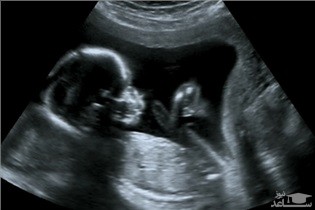

بررسی 986 زن بومی در بولیوی نشان داد، نوعی انگل به نام «کرم حلقوی بزرگ» یا «آسکاریس لوبریکوئیدس» با تغییر دادن سیستم ایمنی بدن باعث میشود زنها بارورتر شوند.